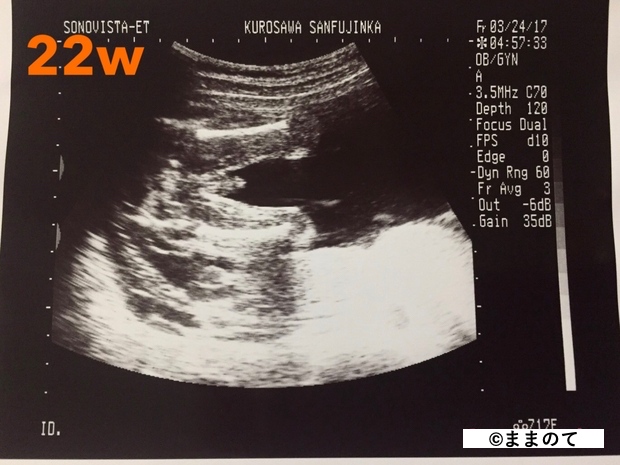

妊娠6ヶ月(20・21・22・23週)

赤ちゃんの骨格や顔立ちがしっかりしてきます。羊水を飲んで呼吸の練習を開始します。心臓が完成してくるため、エコー写真には心臓の弁の動きがはっきりと写し出されます。

身長は約30cm、体重は600~650gほどです。まだ脂肪は多くありませんが、3Dエコーや4Dエコーで全身が見られる時期のため、記念に受診する人もいるようです。

上のエコー写真では、股間からおちんちんが出ているのが見え、男の子だということがわかります。